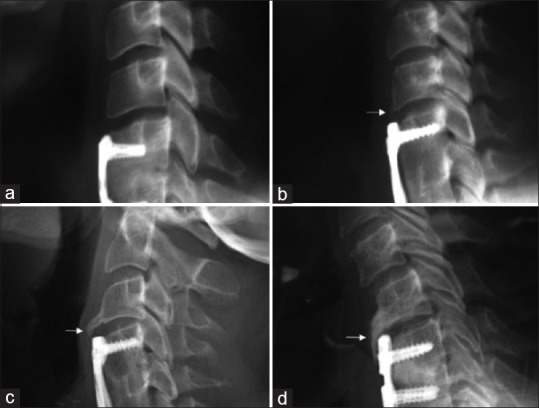

Subjects and methods: We analyzed 63 patients with ACDF with a minimum of 2 years of follow-up. In the imaging evaluation, sagittal balance parameters were included, as well as radiographic parameters that target the development of ASDeg. In addition, discrimination was made between arthrodesis techniques.

Results: Patients with postoperative imbalance presented with radiographic ASDeg at a rate of 26% (n = 5) versus 22% (n = 9) in patients with postoperative balance, this difference was not significant (P = 0.7). In those who underwent surgery with plate, we found that 23% (n = 4) developed ASDeg versus 22% (n = 1) of patients with anterior cervical arthrodesis with cage-plate and 27% (n = 10) of patients who underwent interbody device surgery, with this difference being nonsignificant (P = 0.7).

Conclusion: We concluded that neither postoperative imbalance nor the type of arthrodesis in patients undergoing ACDF for degenerative pathology showed a positive correlation with the development of radiographic cervical ASDeg at an average follow-up of 8 years.